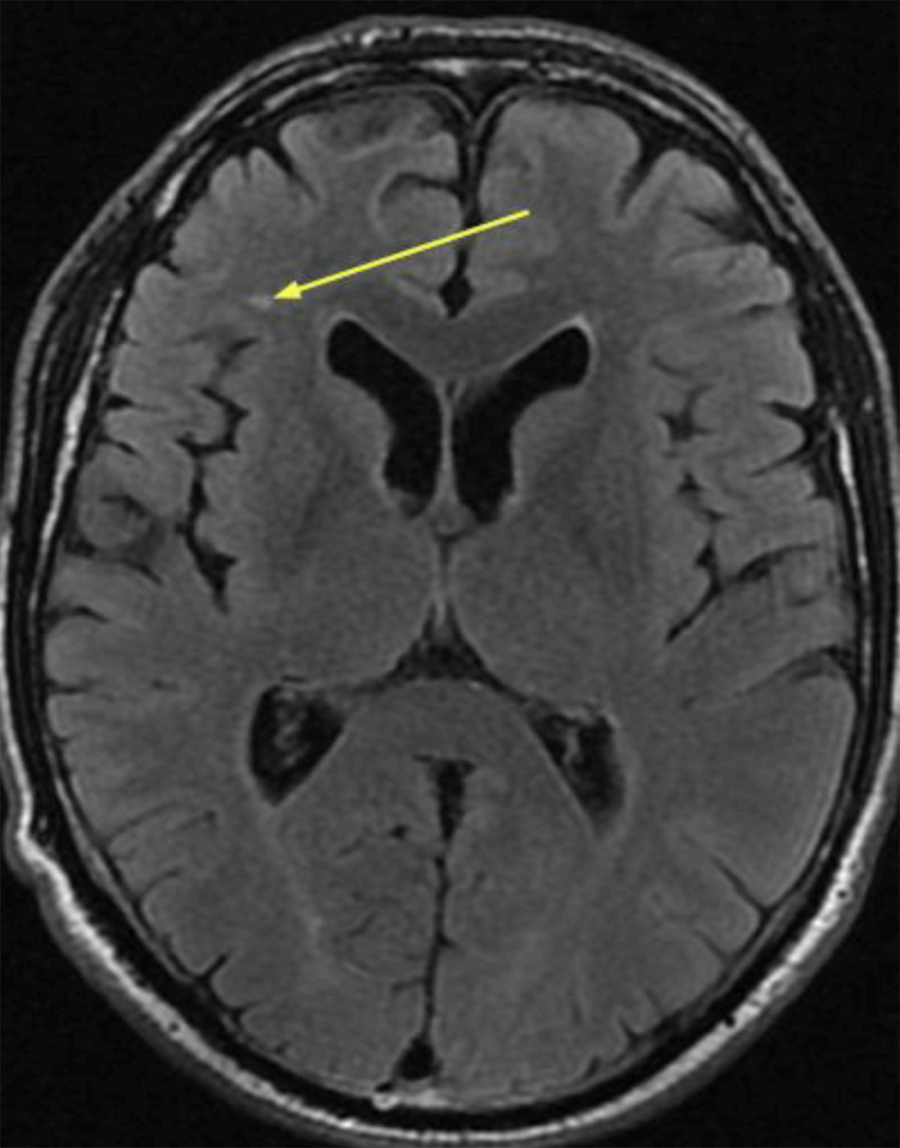

Иллюстрации и пояснения: гиподенсивный очаг на КТ головного мозга

Раздел: Кадры перемен